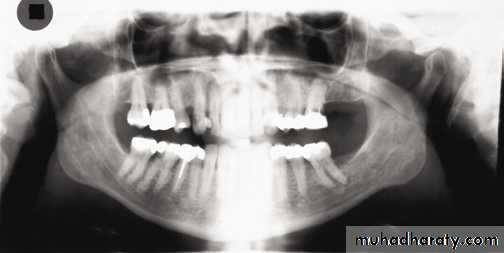

1, Mandibular condyle. 2, Articular eminence. 3, Coronoid process of mandible superimposed on zygomatic arch. 4, Posterior wall of maxillary sinus. 5, Posterior wall of zygomatic process of maxilla. 6, Hard palate. 7, Nasal septum. 8, Tip of nose. 9, Dorsum of tongue. 10, Hyoid superimposed over inferior border of mandible. 11, Inferior border of maxillary sinus. 12, Image of cervical spine. 13, Medial border of maxillary sinus. 14, Infraorbital canal. 15, Infraorbital rim. 16, Pterygomaxillary fissure. 17, Anterior border of the pterygoid plates. 18, Lateral pterygoid plate superimposed over soft palate and coronoid process of mandible. 19, Ear lobe. 20, Inferior border of mandibular canal. 21, Mental foramen. 22, Posterior wall of nasopharynx. 23, Inferior border of mandible superimposed from opposite side. 24, Soft palate over mandibular foramen of mandible.